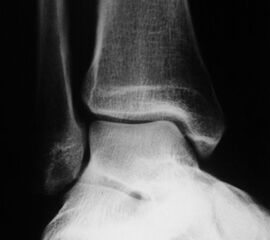

Röntgenaufnahmen dienen primär dem Ausschluss einer knöchernen Verletzung. Die Beurteilung der Geometrie der Malleolengabel kann einen ersten Hinweis auf eine Syndesmosenverletzung liefern. Die notwendigen Röntgenaufnahmen umfassen das Sprunggelenk anterior-posterior, lateral und in 20° Innenrotation (Mortise view). Zur Beurteilung der Syndesmose sind verschieden Parameter in der Mortise view beschrieben. Zu diesen zählen der tibiofibulare Clearspace, der mediale Clearspace, sowie die Überlappung der distalen Fibula und Tibia im Bereich der Incisura (Abbildung 2). Der Tibiofibulare Clearspace wird als verlässlichster Indikator für eine Syndesmosenverletzung gesehen, da er nicht signifikant von der tibialen Rotation beeinflusst wird 32. Er wird 1 cm proximal des Tibiaplafonds gemessen und sollte weniger als 6mm betragen 33. Jede Messung, die diesen Wert übersteigt, stellt einen Hinweis für eine Syndesmosenverletzung dar. Eine tibiofibulare Überlappung von 6 mm oder mehr in der AP Aufnahme, sowie mehr als 1 mm in der Mortise View Aufnahme gelten als physiologisch 33. Der mediale Clearspace sollte nicht mehr als 4 mm betragen 34.

Abbildung 3 zeigt ein Sprunggelenk nach Syndesmosenverletzung mit einem erweiterten Tibiofibularen Clearspace.

Die über viele Jahre empfohlenen gehaltenen Aufnahmen haben ihre Bedeutung vollständig verloren (Szeimies 2013). Sensitivere Diagnostikmöglichkeiten wie z.B. die Magnetresonanztomographie und eine zu hohe Falsch-Negativ Rate sind dafür verantwortlich 3536.